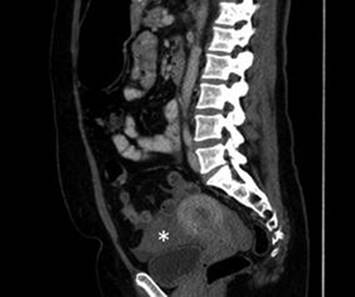

Ruptured Ovarian Cyst

On physical examination, patients may have signs of peritoneal irritation due to free fluid in the abdomen, including rebound or cervical motion tenderness; patients are generally afebrile, without an elevated white blood cell count [50]. By transvaginal ultrasound, patients may have simple or complex free fluid in the pelvis, particularly the posterior cul-de-sac; the originating cyst is seldom visualized [47]. A CT scan will also reveal hemoperitoneum, but is often unnecessary with appropriate history, physical exam, and targeted ultrasound; if a CT is performed with intravenous contrast, active contrast extravasation from the ovary may rarely be visualized (Fig. 4.16).

Fig. 4.16

Ovarian cyst rupture. CT scan showing moderate complex free fluid, indicated with an asterisk (*), consistent with hemoperitoneum due to ovarian cyst rupture